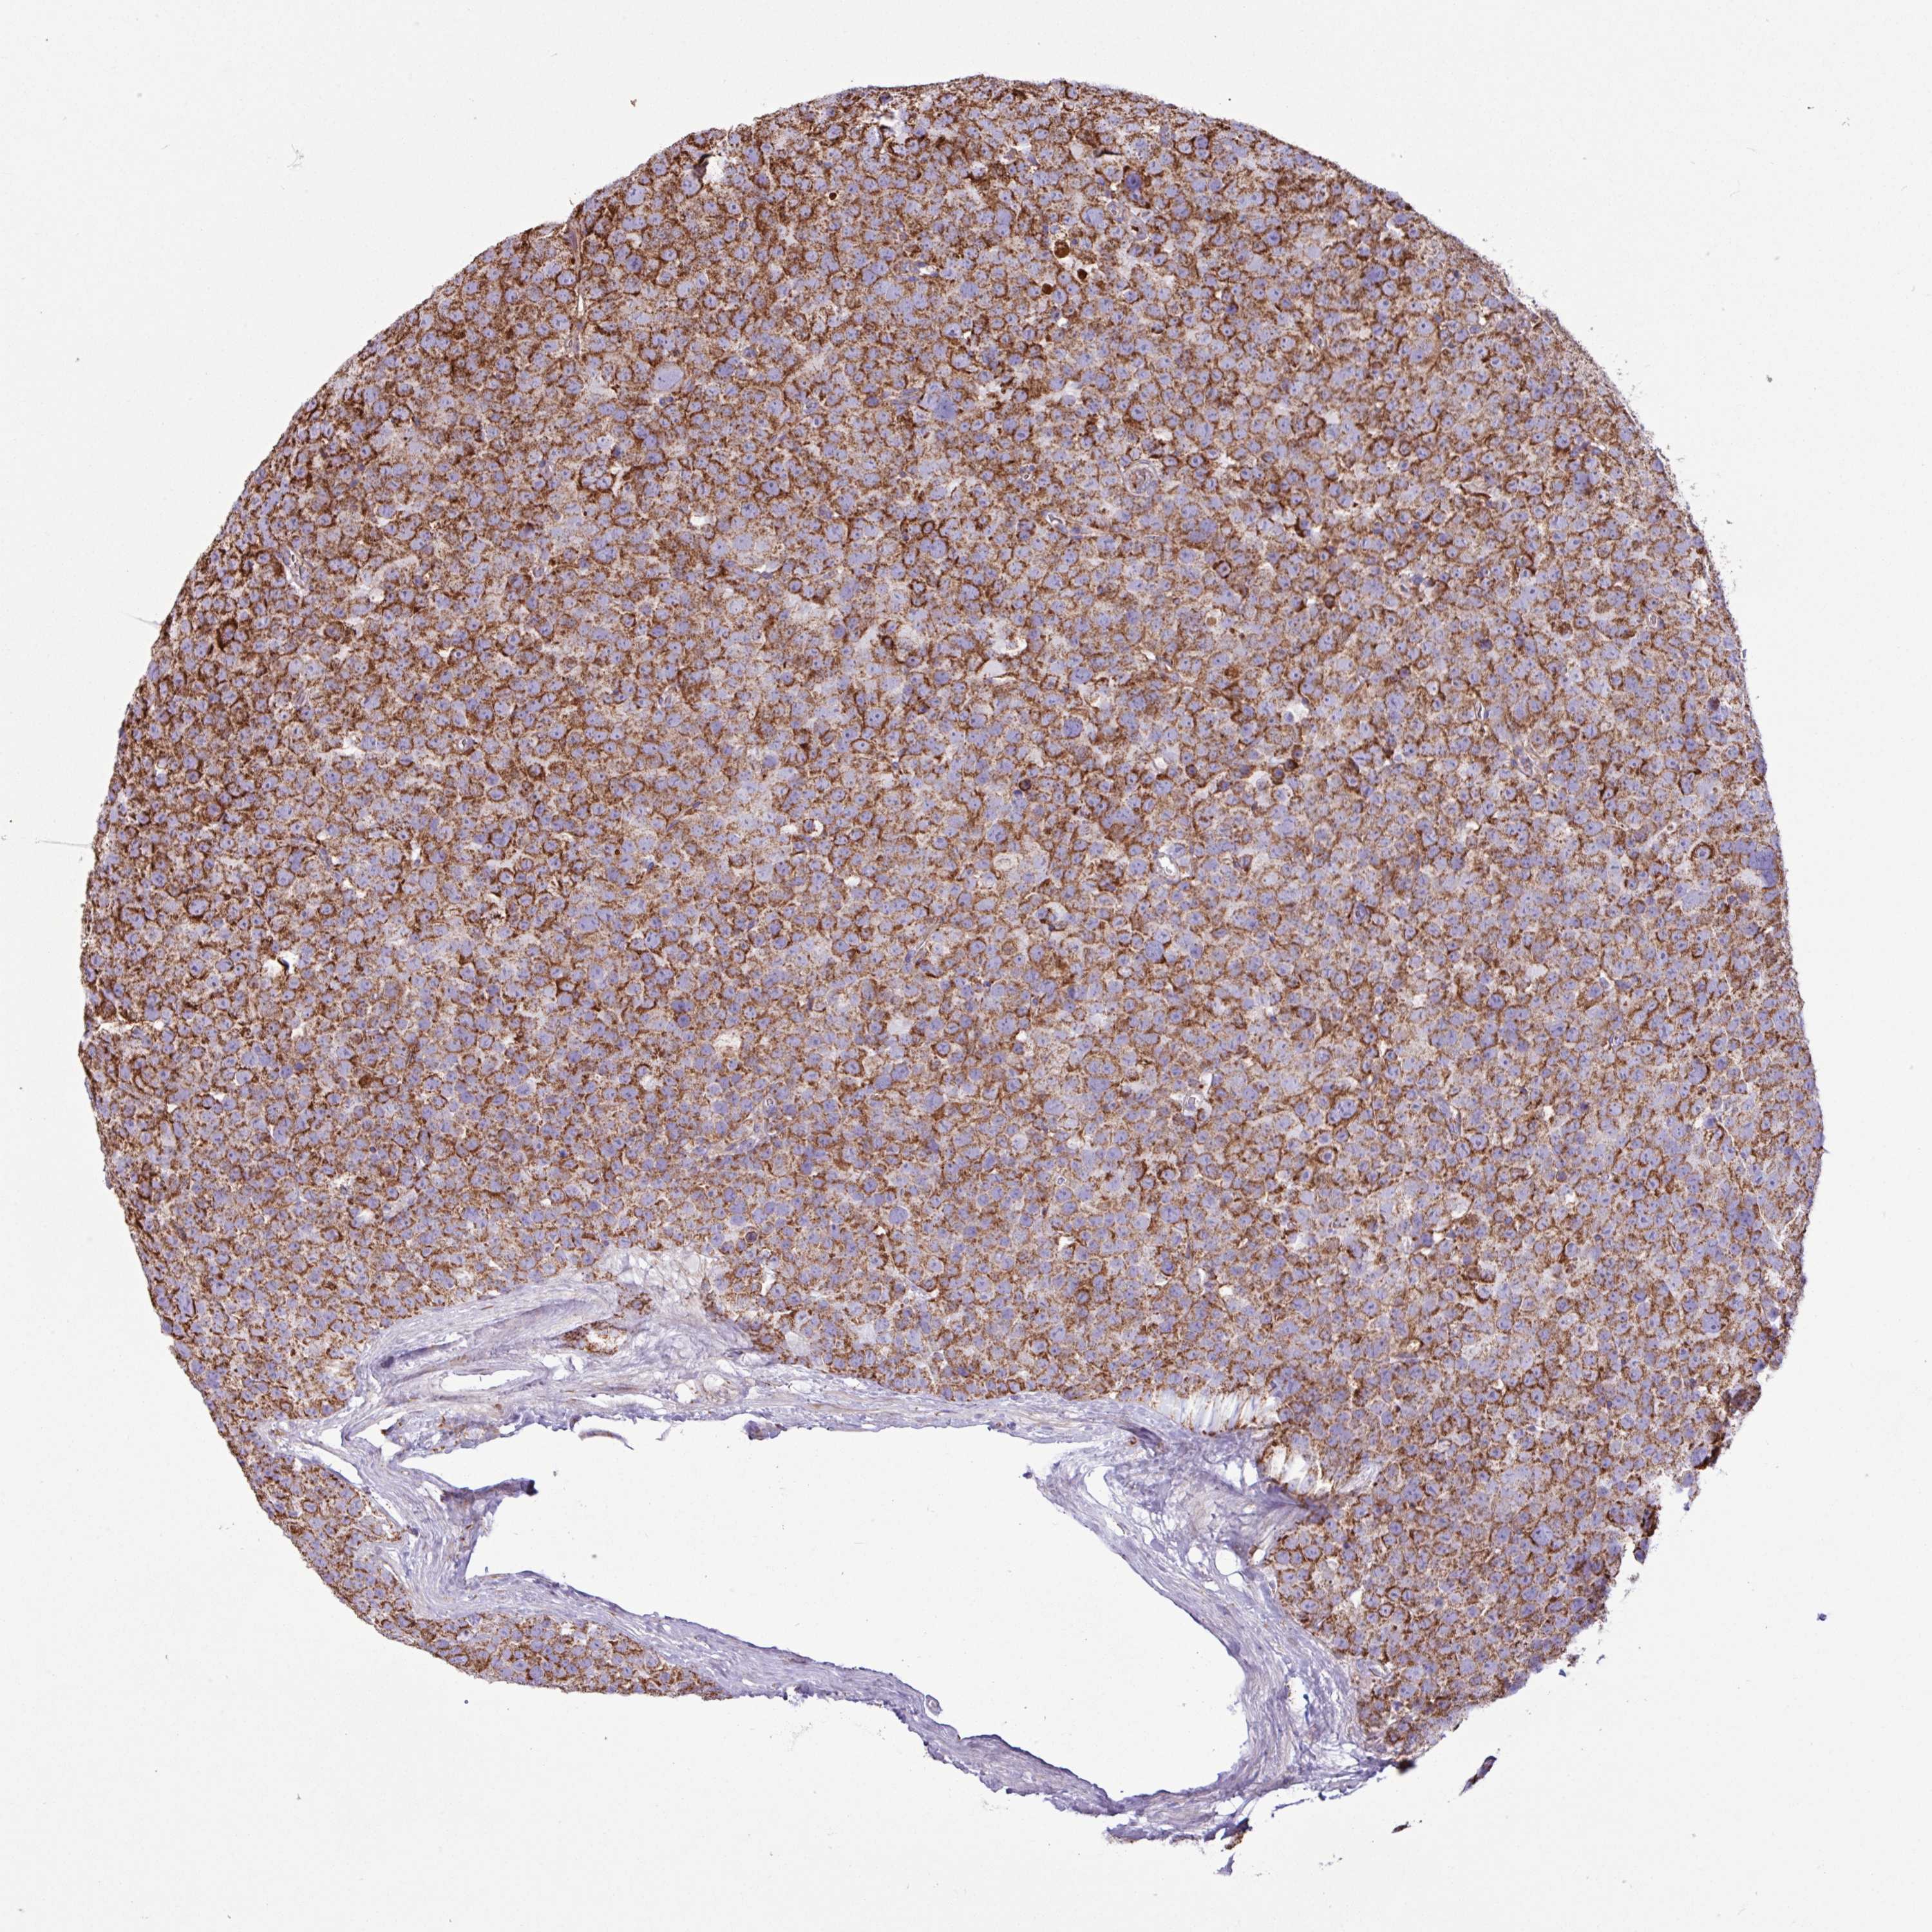

TESTIS CANCER - Protein expressioni

A mouse-over function shows sample information and annotation data. Click on an image to view it in a full screen mode. Samples can be filtered based on level of antibody staining by selecting one or several of the following categories: high, medium, low and not detected. The assay and annotation is described here.

Note that samples used for immunohistochemistry by the Human Protein Atlas do not correspond to samples in the TCGA dataset.

Antibody stainingi

Antibody staining in the annotated cell types in the current human tissue is reported as not detected, low, medium, or high, based on conventional immunohistochemistry profiling in selected tissues. This score is based on the combination of the staining intensity and fraction of stained cells.

Each image is clickable and will lead to virtual microscopy that enables deeper exploration of all samples and also displays staining intensity scores, fraction scores and subcellular localization as well as patient and tissue information for each sample.

Antibody HPA051991

Antibody HPA053174

Staining

High

Medium

Low

Not detected

Intensity

Strong

Moderate

Weak

Negative

Quantity

>75%

75%-25%

<25%

None

Location

Nuclear

Cytoplasmic/membranous

Cytoplasmic/membranous,nuclear

Seminoma, NOS

Carcinoma, Embryonal, NOS